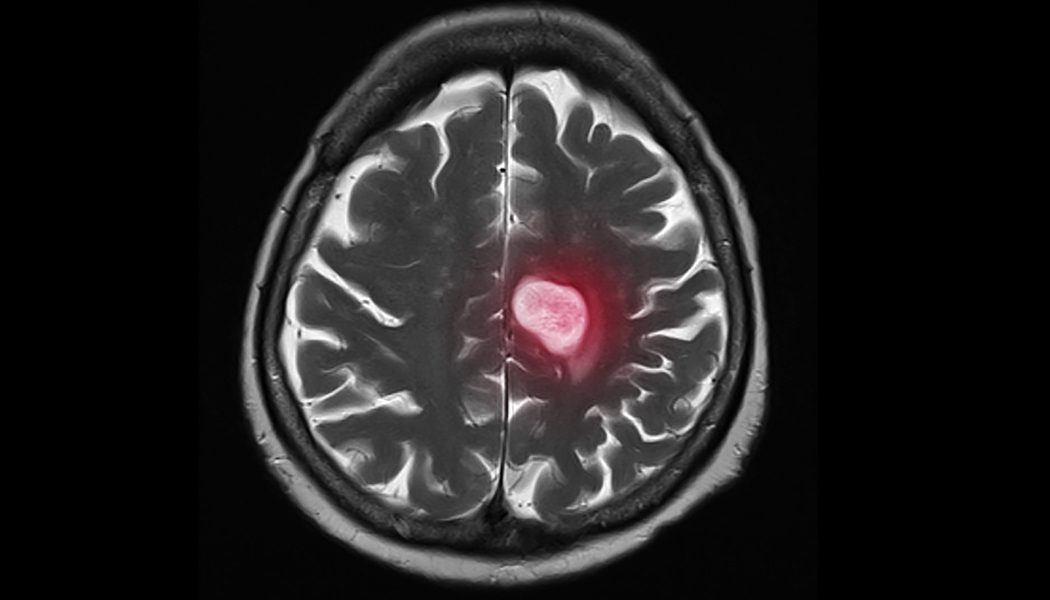

Di căn hệ thần kinh trung ương (TKTW) ở các bệnh nhân ung thư phổi không tế bào nhỏ (UTPKTBN) có hoặc không các đột biến gen phù hợp với các liệu pháp nhắm trúng đích vẫn luôn đặt ra thách thức cho các bác sĩ lâm sàng.

Nhìn chung, tổn thương thứ phát tại TKTW gặp phổ biến hơn ở nhóm có đột biến khi có khoảng 28 – 65% trường hợp có đột biến EGFR và 34% trường hợp sai lệch ALK được phát hiện di căn não – màng não tại thời điểm chẩn đoán.

Thậm chí, những người bệnh chưa có tổn thương TKTW tại thời điểm ban đầu, cùng với thời gian sống thêm được kéo dài nhờ hiệu quả của các liệu pháp nhắm trúng đích, cũng sẽ phải đối diện với nguy cơ cao bệnh tiến triển di căn não hoặc có đến 5% trường hợp sẽ xuất hiện di căn màng não.